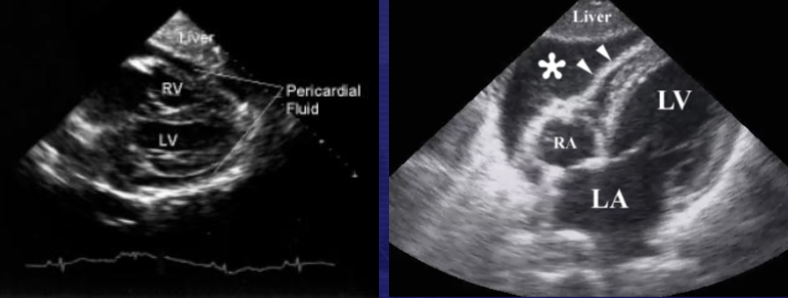

What is being evaluated on a FAST scan if the transducer is in the subxyphoid area (angle superiorly from just inferior to the xyphoid process)?

Pericardial effusion

Presence of fluid within the pericardium